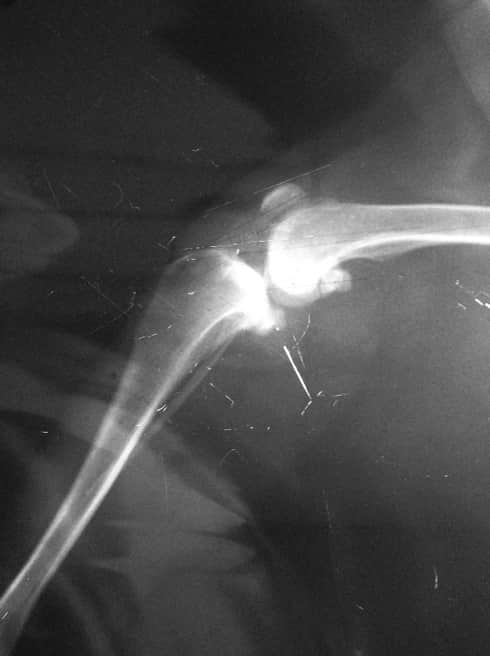

我问诊,是否以膝关节内侧肿胀为主?是否外侧无肿胀,抽屉运动是否异常?回答均乎。于是拟诊断为前十字韧带断裂或部分断裂,内侧半月板损伤。由于考虑到年龄和体重,建议施胫骨粗隆前移手术,以稳定膝关节,减缓半月板压力。同时进行生物陶瓷填充物植入。

术前,我们的冼医生为之进行了简单的理学检查。我们重新拍摄了膝关节x光,计算了手术的植入物宽度。准备好之后,我们开始对动物麻醉,上了监护。在消毒好,我们手术开始了十分钟之前,任麻醉师的冼医生示意让我停止手术。我不解,但必须听指挥。要知道,手术中最高权力者非主刀医师,而是麻醉师。